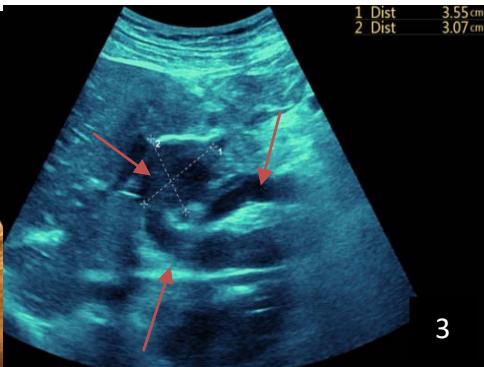

Iconography 1: 54-year-old patient with an intra-splenicsolid mass, anatomopathologically compatible with lymphoma: images 1 and 2: right pleurisy of moderateabundance, image3: celiacadenopathy, image 4: free ascites of moderateabundance, images 5 and 6: intra-splenicsolid mass of around $1418.16\mathrm{ml}$ in B mode and elastographyshowing areas of tumourrigidity, images 7-10: oblique linear images, showingbiopsy gun tracks.